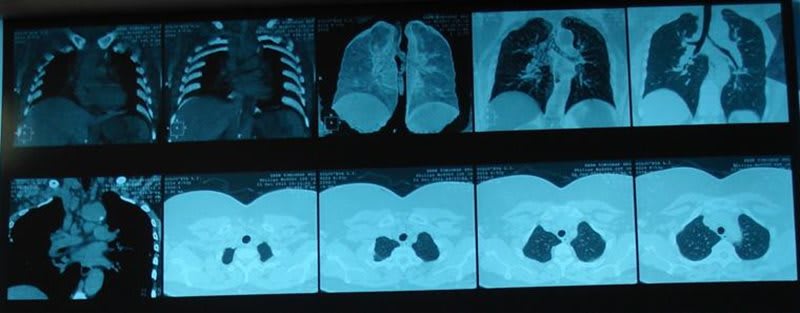

4. Рентгенографические показатели интерстициальной болезни, соответствующие фиброзно-очаговому процессу.

5. Признаки фиброза легких, обструктивного поражения дыхательных путей или пониженной способности к диффундированию окиси углерода.

Хроническая бериллиевая болезнь (ХББ) может развиваться в течение десятилетий после прекращения экспозиции к данному веществу и представляет собой прогрессирующее гранулематозное заболевание, которое может привести к снижению дыхательного объема легких, одышке и к диффузным неоднородным затемнениям на рентгенограмме. Для ХББ характерна клеточно-опосредованная иммунная реакция.

Бериллиоз – это профессиональное заболевание с преимущественным поражением дыхательной системы, возникающее в результате вредного воздействия соединений бериллия на организм. Острый бериллиоз протекает по типу бронхита или пневмонии. Хронический процесс характеризуется постепенно нарастающим кашлем, одышкой, выраженной астенизацией и признаками интоксикации. Диагностика основывается на данных анамнеза, рентгенографии и КТ грудной клетки, кожных и серологических тестов, исследовании биопсийного материала. Назначается лечение кортикостероидами, антигистаминными и противокашлевыми препаратами.

При подозрении на бериллиоз большое диагностическое значение имеет установление контакта пациента с бериллиевыми парами или пылью в анамнезе. При осмотре обращает на себя внимание акроцианоз либо диффузный цианоз кожных покровов. Иногда обнаруживаются подкожные гранулёмы. Дыхание учащенное, одышка усиливается при незначительной физической нагрузке и разговоре. Наблюдается дистальная гипертрофическая остеоартропатия. Пальпируются увеличенные лимфатические узлы. Характерным признаком бериллиоза является увеличение локтевых лимфоузлов до размера горошины. Для окончательного подтверждения диагноза выполняются:

Хронический бериллиоз дифференцируют с диссеминированным туберкулёзом, саркоидозом Бека, метастатическими поражениями органов дыхания, другими пневмокониозами. По показаниям назначают консультации фтизиатра и онколога, проводят иммунодиагностические тесты (проба Манту, Диаскинтест), исследуют мокроту на БК. В неясных случаях осуществляют биопсию лёгкого с дальнейшим гистологическим исследованием полученного материала.

На рентгенограмме можно определить симптомы развивающейся эмфиземы легких, диффузного бронхита и бронхиолита. Увеличивается частота сердечных сокращений, на рентгенограмме отмечается выраженное увеличение границы сердца вправо, в легких резко увеличивается контрастность сосудистого рисунка, и по всем легочным полям заметно большое количество различных округлых теней;